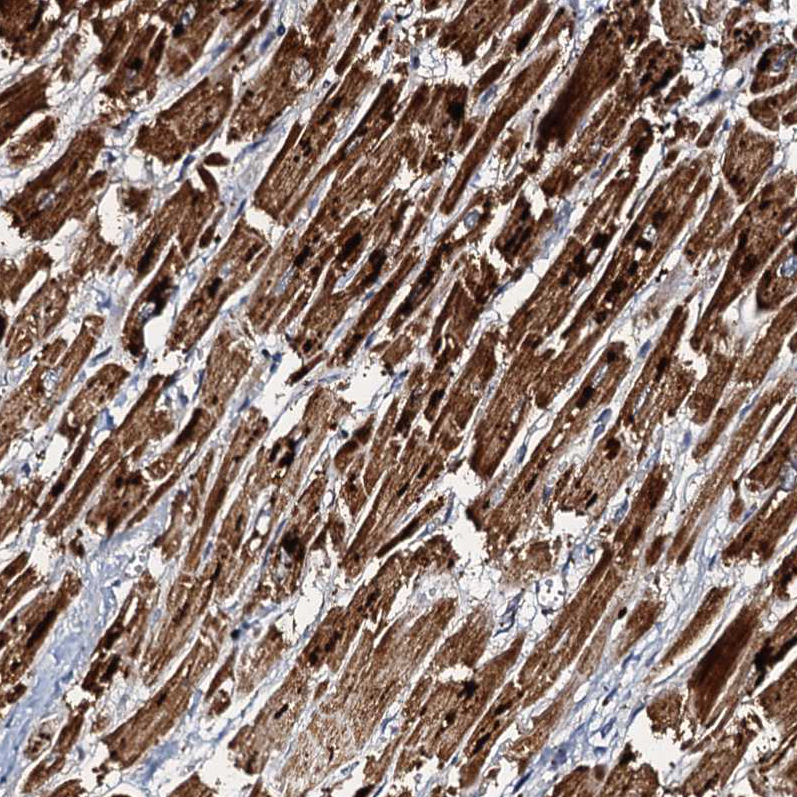

Immunohistochemical staining of human heart muscle shows strong granular cytoplasmic positivity in cells in cardiomyocytes.